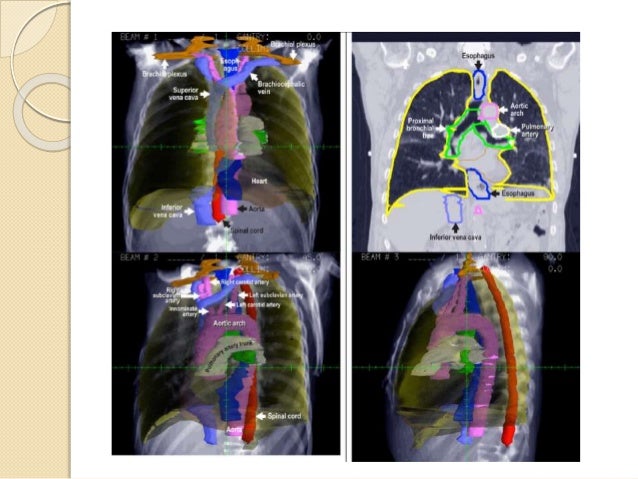

Side effects lung and trachea heart esophagus spinal cord radiation to the lung and trachea can lead to coughing, or shorteness of breath, if the esophagus cancer is invading into the trachea there is a risk of a fistula (te fistula) stomach structures affected by radiation long terms risks are related to scarring or fibrosis in the lung which. However, a large portion of. Since that time, telecobalt has been utilized in these cases.

Local control can be achieved with higher brachytherapy. The authors examine the role of radiation therapy alone (external beam and brachytherapy) for the management of esophageal cancer or combined with other modalities. The cervical esophagus extends from the upper esophageal sphincter to the thoracic inlet.

The authors examine the role of radiation therapy alone (external beam and brachytherapy) for the management of esophageal cancer or combined with other modalities. Memorial sloan kettering has been a leader in improving radiation therapy for esophageal cancer. The esophagus is divided into four regions by the ajcc.